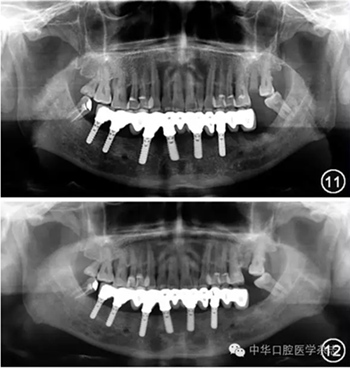

即刻種植后,常規(guī)的治療方案是在永久修復(fù)體戴入前采用臨時活動義齒修復(fù)作為過渡(圖5~12)。近年來,隨著種植體表面處理方法的改良以及種植外科與修復(fù)技術(shù)的進步,即刻種植后即刻修復(fù)或即刻負(fù)載在臨床上的應(yīng)用取得了成功。系統(tǒng)性回顧在2年的觀察期內(nèi),即刻種植即刻負(fù)載與常規(guī)負(fù)載的種植體存留率分別為98.2% 和98.5%,兩組差異無統(tǒng)計學(xué)意義。需要指出的是,在多數(shù)報告即刻種植即刻負(fù)載的研究中,修復(fù)體并沒有正中咬合接觸和側(cè)方咬合接觸,種植體的微動明顯減少。在選擇修復(fù)方式時,需要綜合考慮影響種植體穩(wěn)定性的的外科相關(guān)因素(種植體初期穩(wěn)定性及無創(chuàng)外科技術(shù))、宿主相關(guān)因素(骨質(zhì)與骨量、合適的骨愈合環(huán)境、患者口腔衛(wèi)生和依從性)、種植體相關(guān)因素(種植體宏觀和微觀結(jié)構(gòu)的影響)以及咬合相關(guān)因素(咬合力的控制及修復(fù)體設(shè)計)。